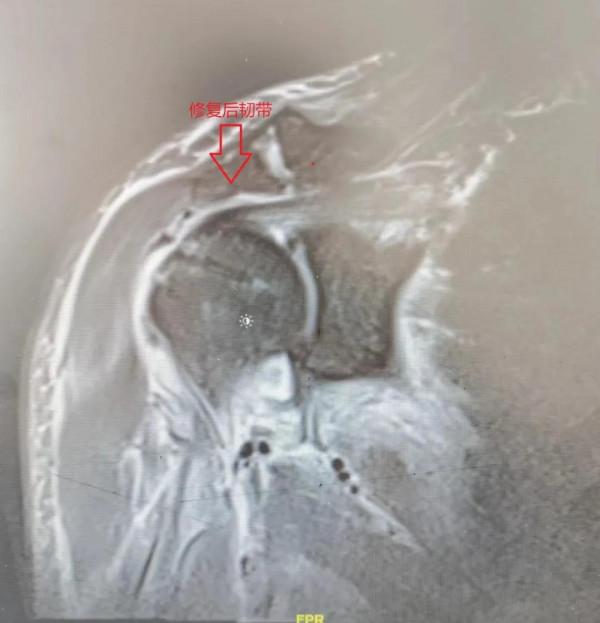

患者術後複查MRI